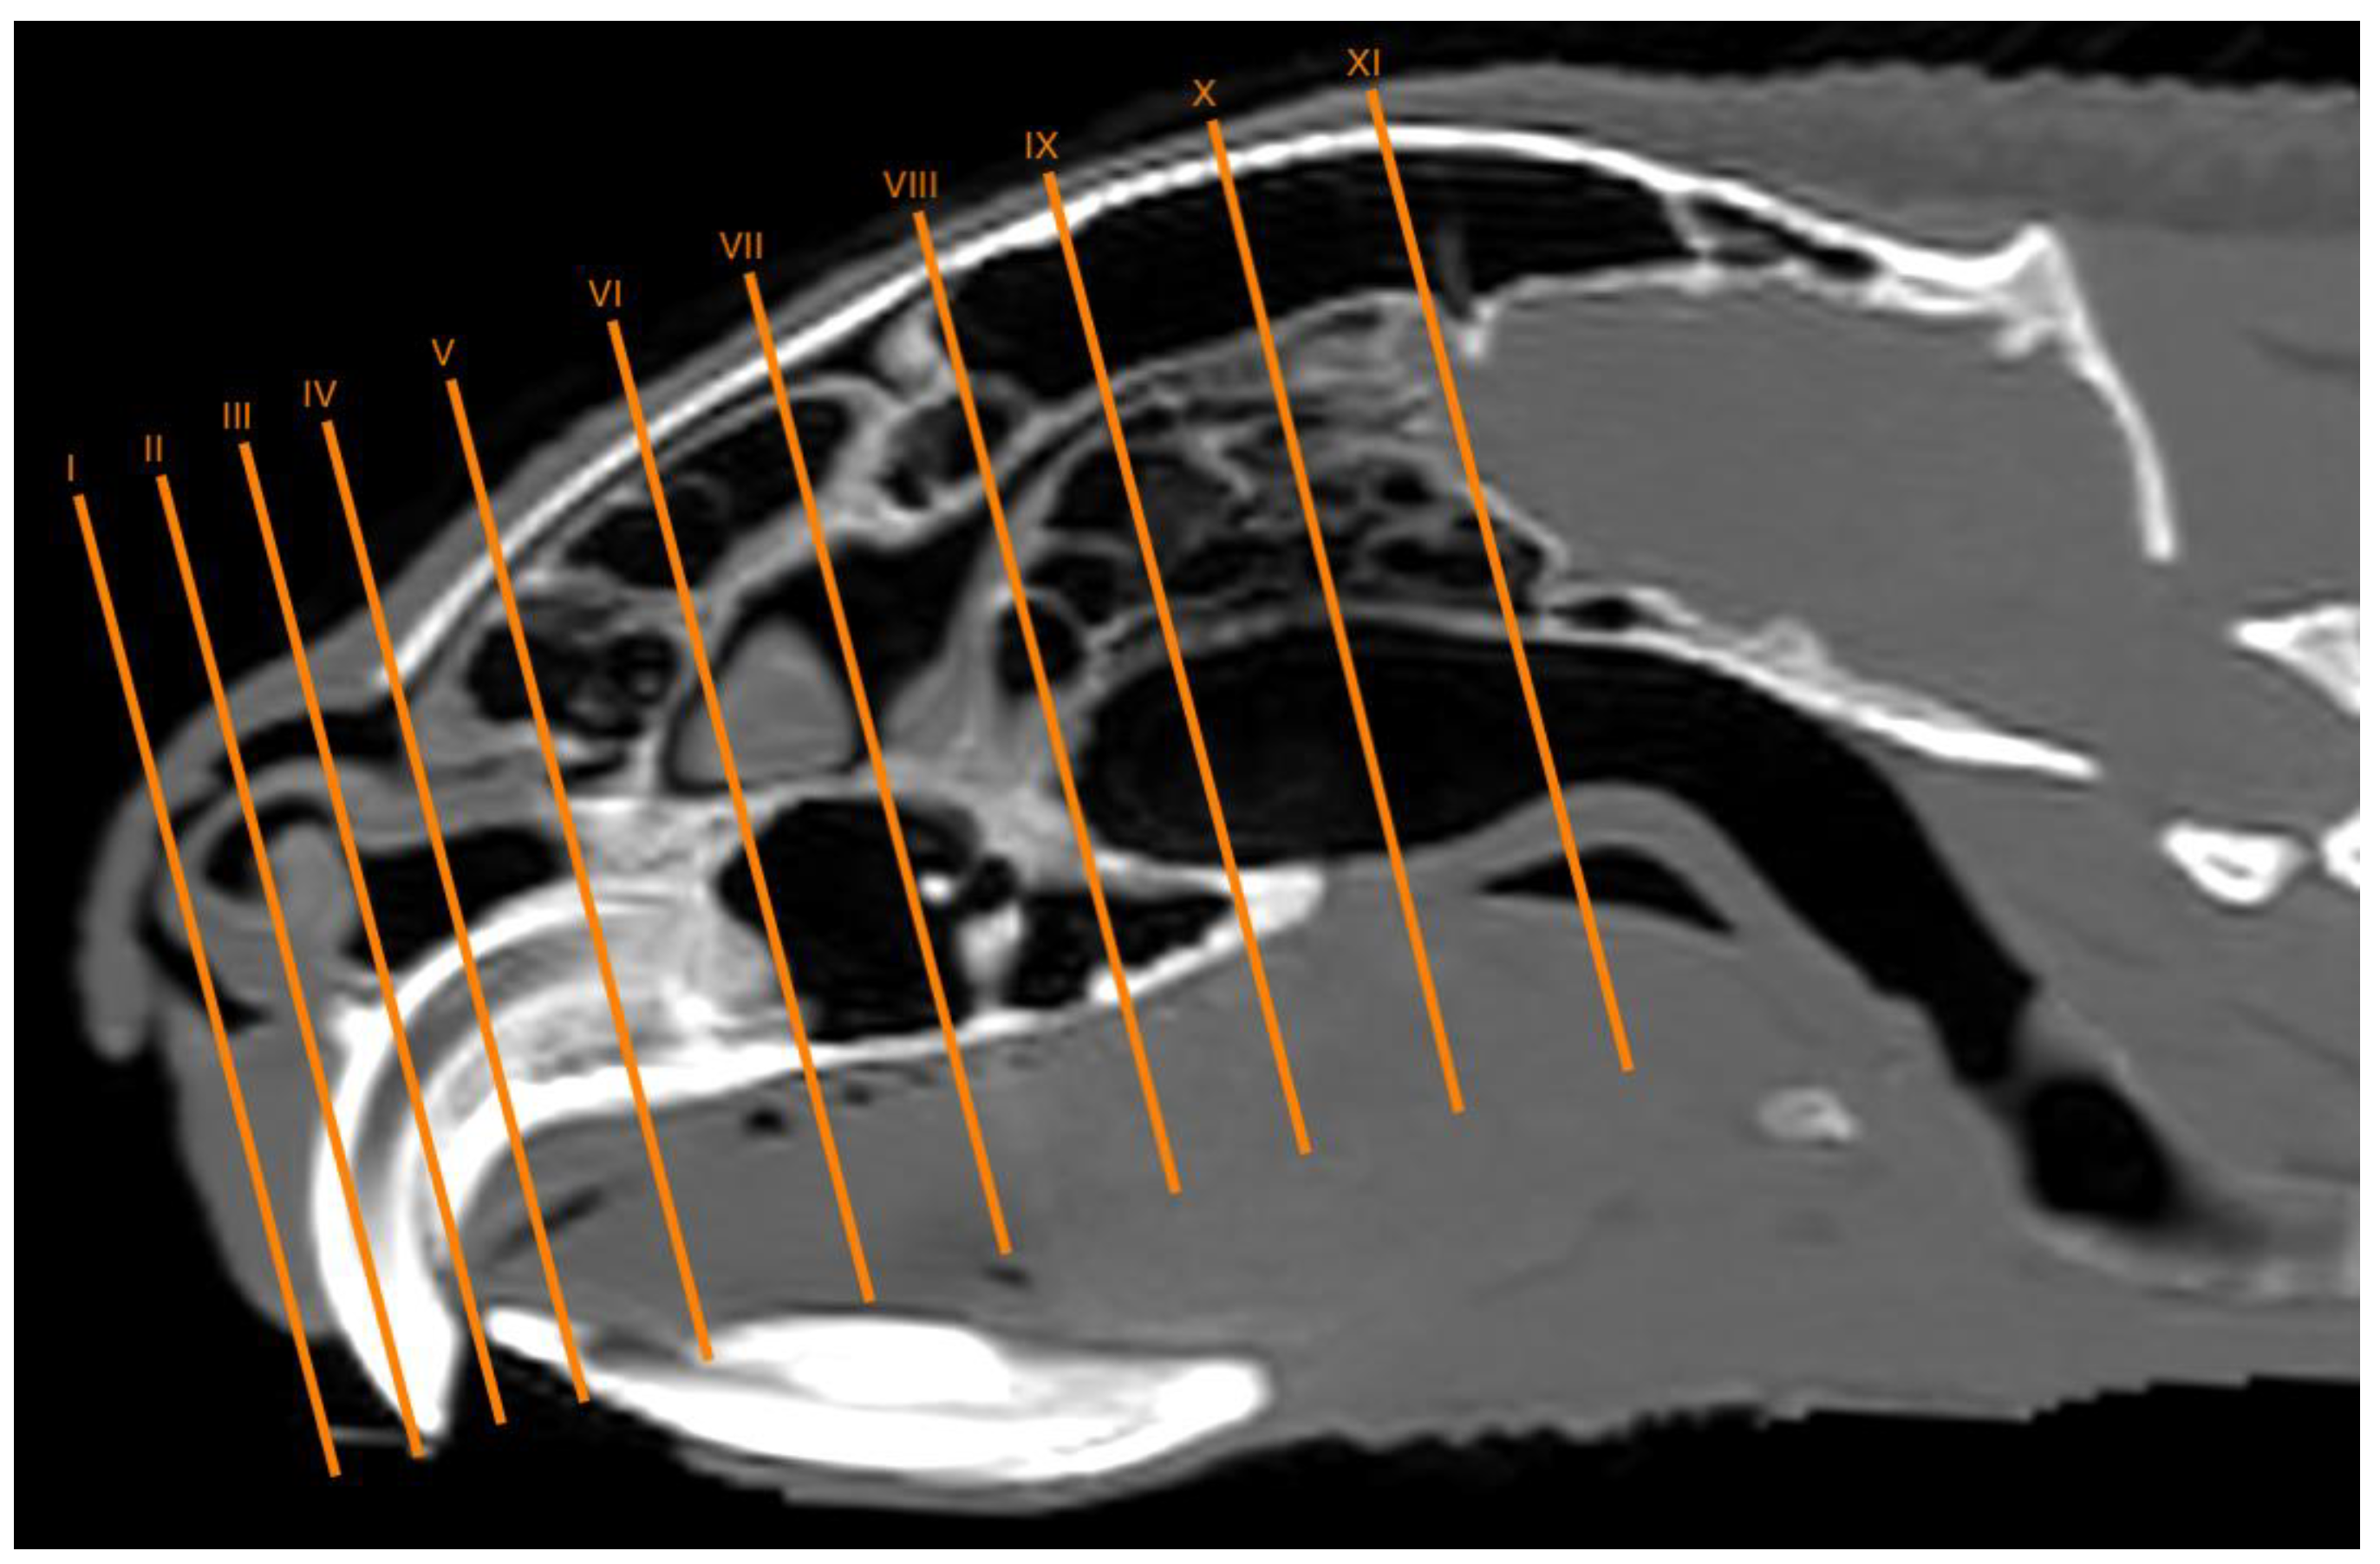

3.1. Anatomical Sections

3.2. Computed Tomography (CT)